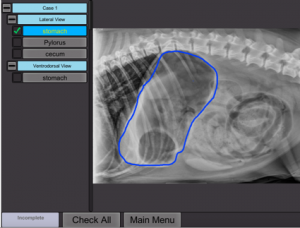

This project is used by veterinary students learning to read and annotate radiographs (x-rays). Instructors can first annotate radiographs. Then, students are given the same opportunity. Afterwards, students’ work is compared to the instructor’s work, which generates a score.

Radiograph Analysis and Annotation